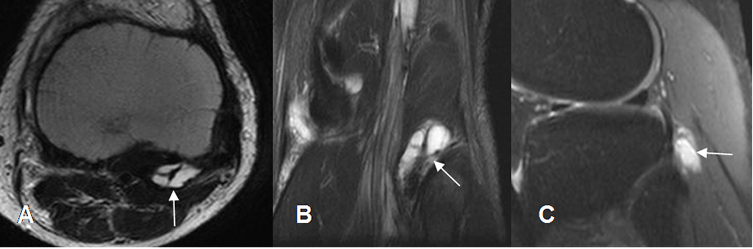

Fig 185. Bursitis del poplíteo.

A: RM axial en T2, B: RM coronal en STIR y C: RM sagital en STIR. Lesión quística en relación con el tendón poplíteo, por bursitis.